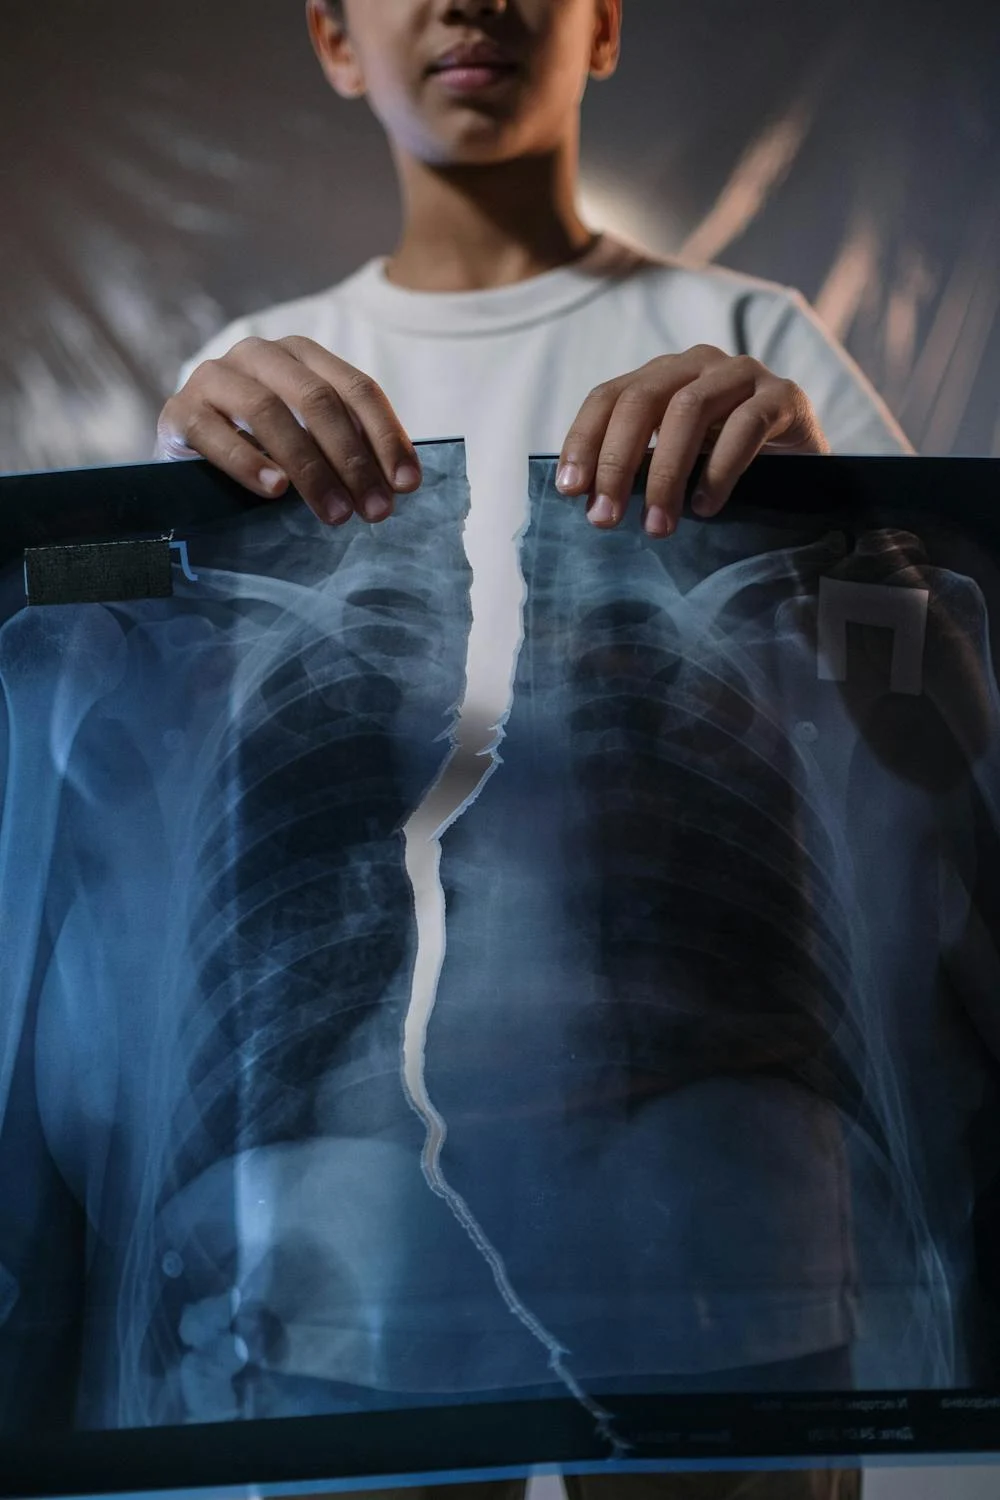

① 흉부 X선 촬영

X선 검사방법으로는 실제 크기로 촬영하는 흉부 직접촬영과 70㎜, 100㎜ 크기의 축소된 사진으로 찍는 간접촬영이 있는데, 여러 사람을 집단으로 검사할 경우에는 간접촬영을 많이 이용합니다.

소견에 따라 초감염 결핵과 재활성화 결핵으로 나뉘며 흔히 전자는 소아 결핵, 후자는 성인 결핵으로 분류하기도 하며 인체면역결핍 바이러스(HIV) 감염자는 초감염 결핵 소견이 주로 나타나는 것으로 알려져 있습니다.